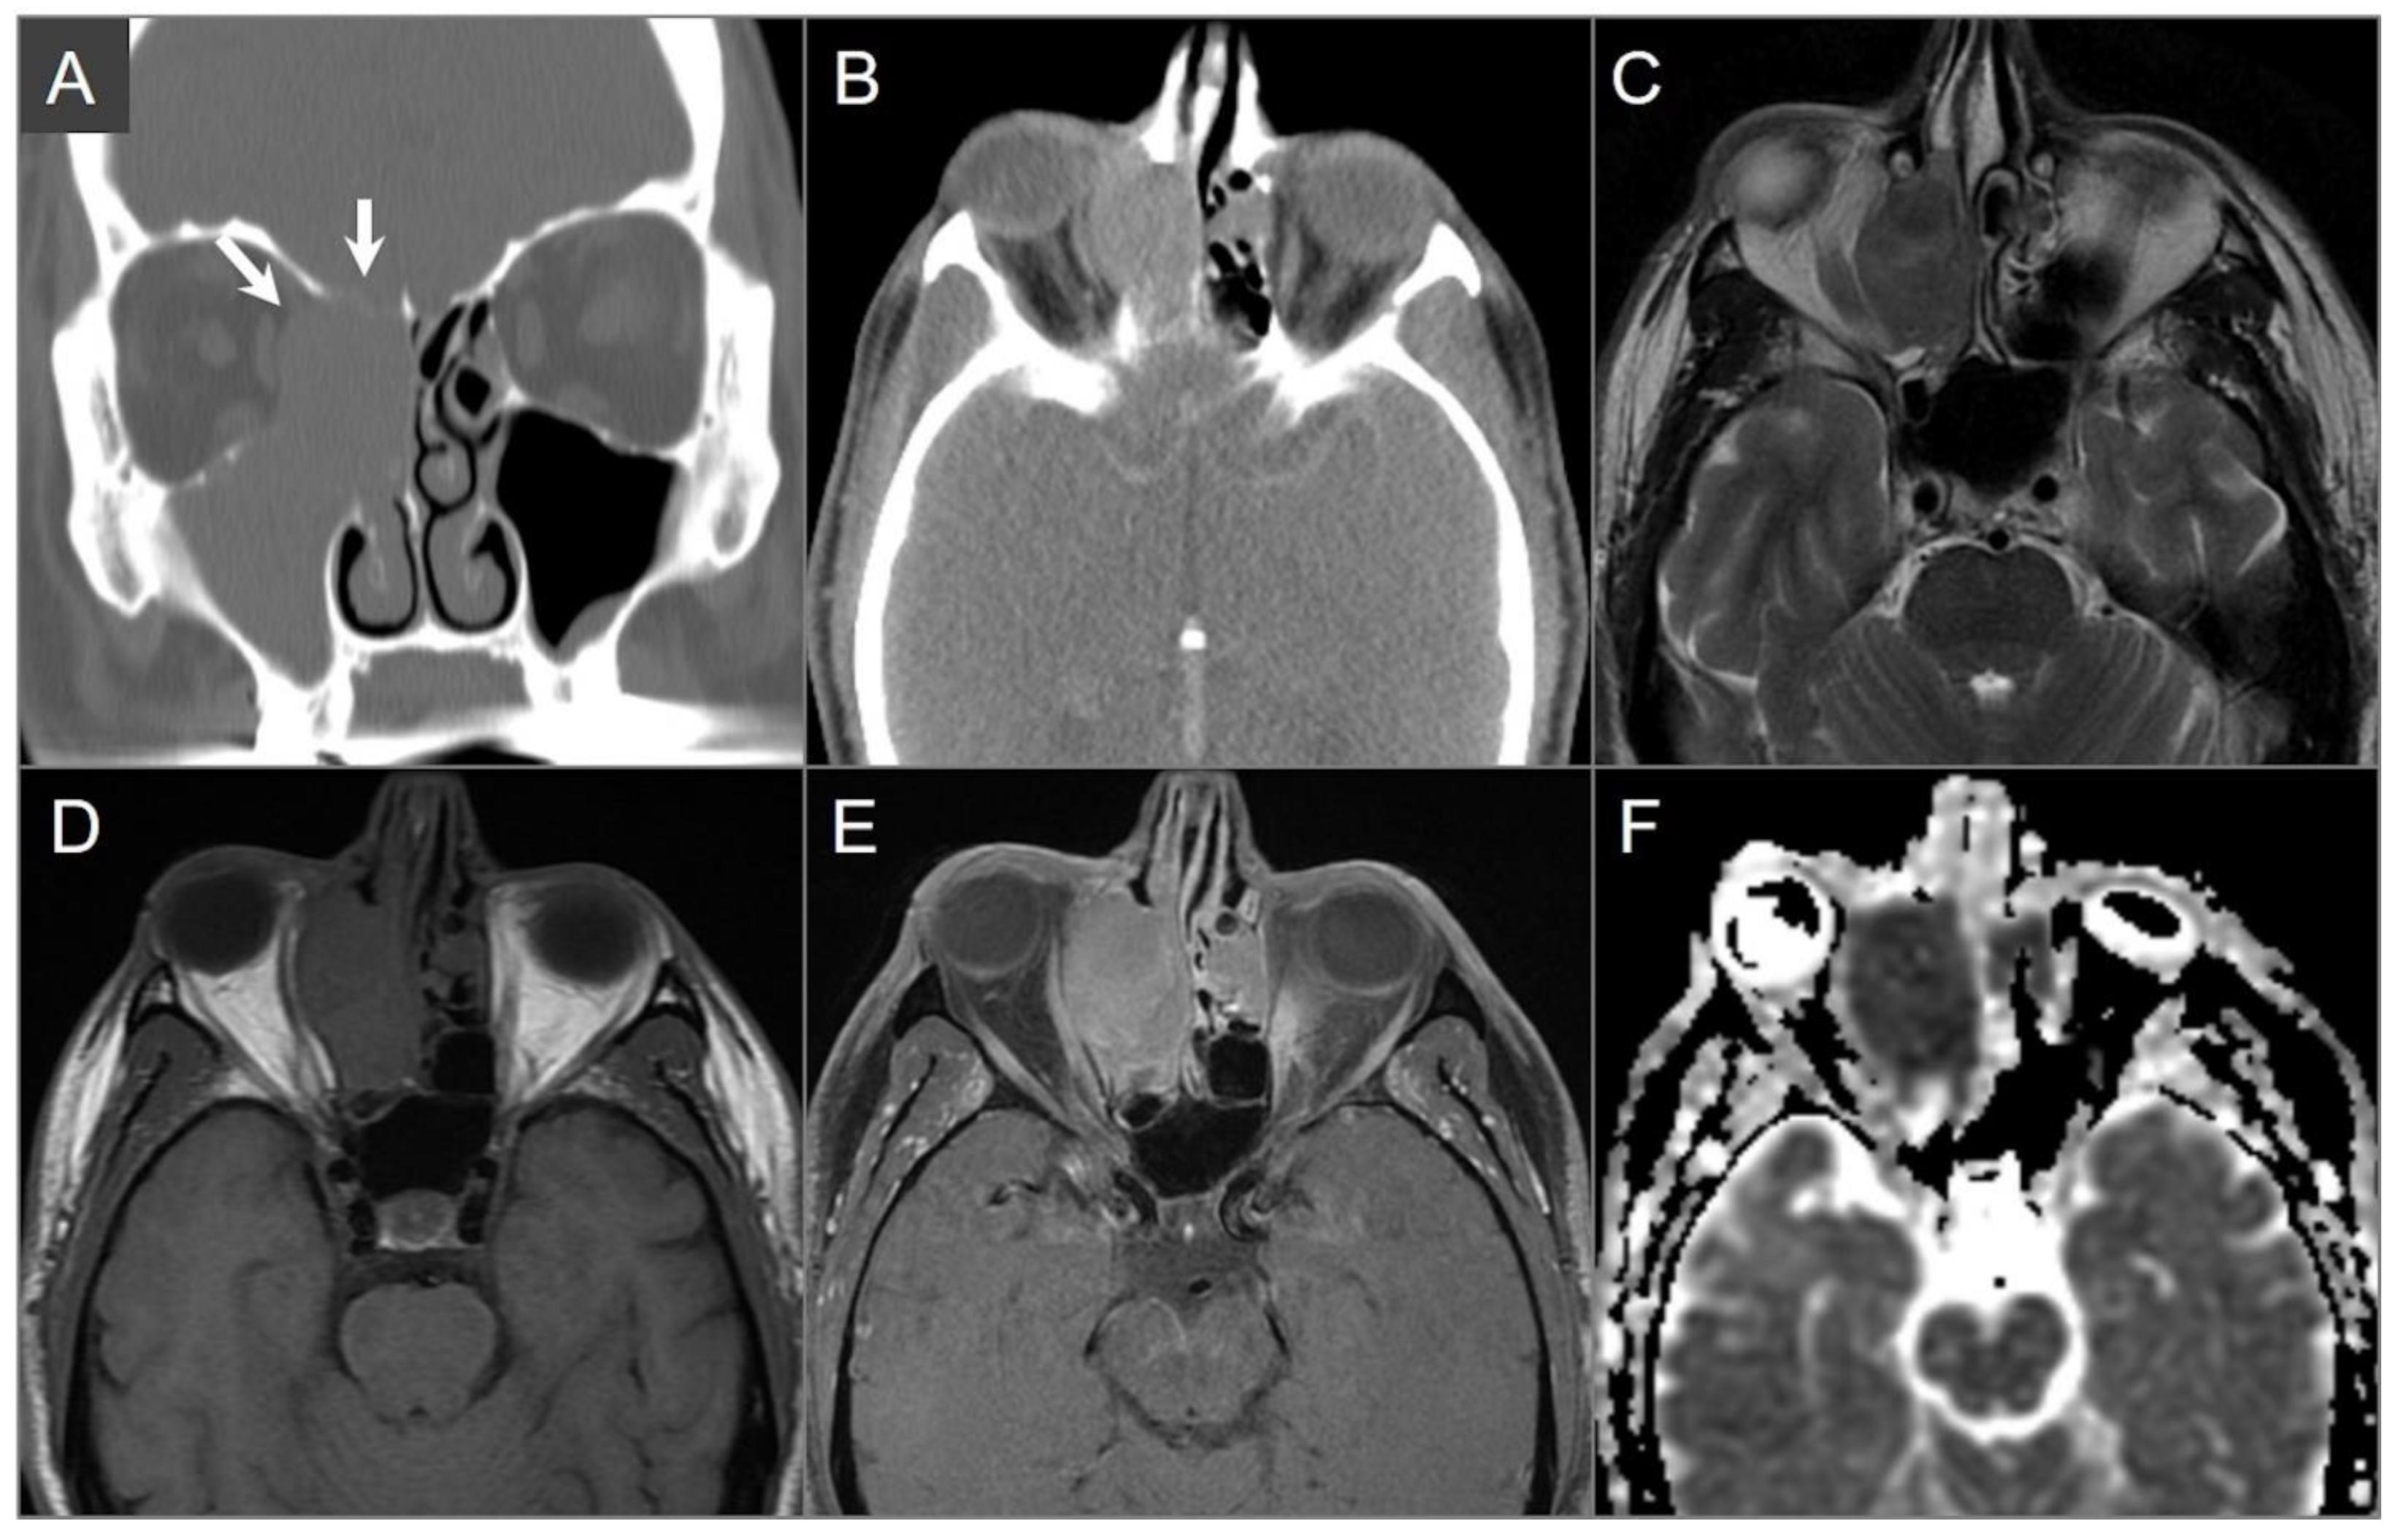

4.2.1. Ossifying Fibroma

4.2.2. Osteoma

4.2.3. Olfactory Neuroblastoma